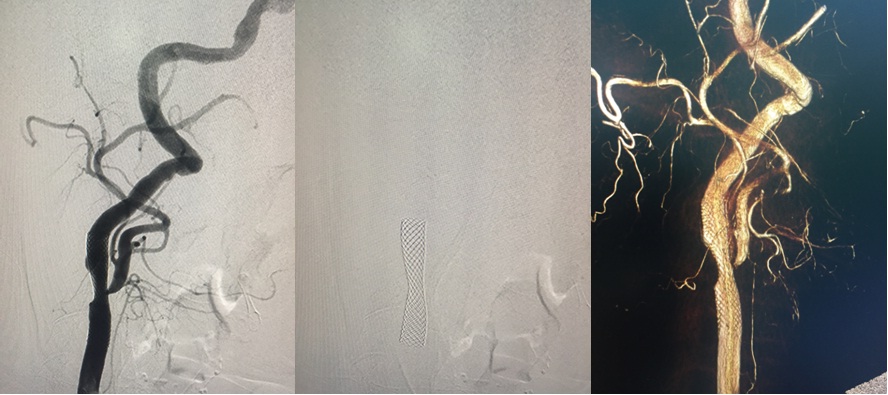

Hình ảnh Động mạch cảnh phải sau Nong và và đặt stent: gốc RICA tái tạo được # 80%.

Bệnh nhân tái khám sau 9 tháng, gốc RICA không tái hẹp, stent chưa thấy bất thường